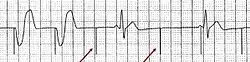

Configuração para fazer um ECG do dispositivo

Configuração para fazer um ECG do dispositivo -